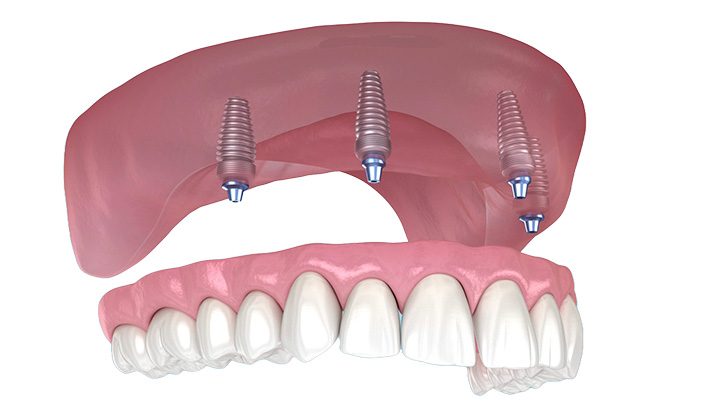

Protesi fissa su 2 - 4 impianti dentali

Innestando almeno due impianti dentali nella mascella inferiore, possiamo fissare la protesi sui localizzatori per renderla fissa. Una soluzione ideale ed economica, la consigliamo a ogni paziente affetto da edentulismo nella mascella inferiore.

Protesi fissa All on 4

Una soluzione innovativa per trasformare rapidamente la mascella edentula in un sorriso funzionale e bello esteticamente con un numero minimo di impianti.